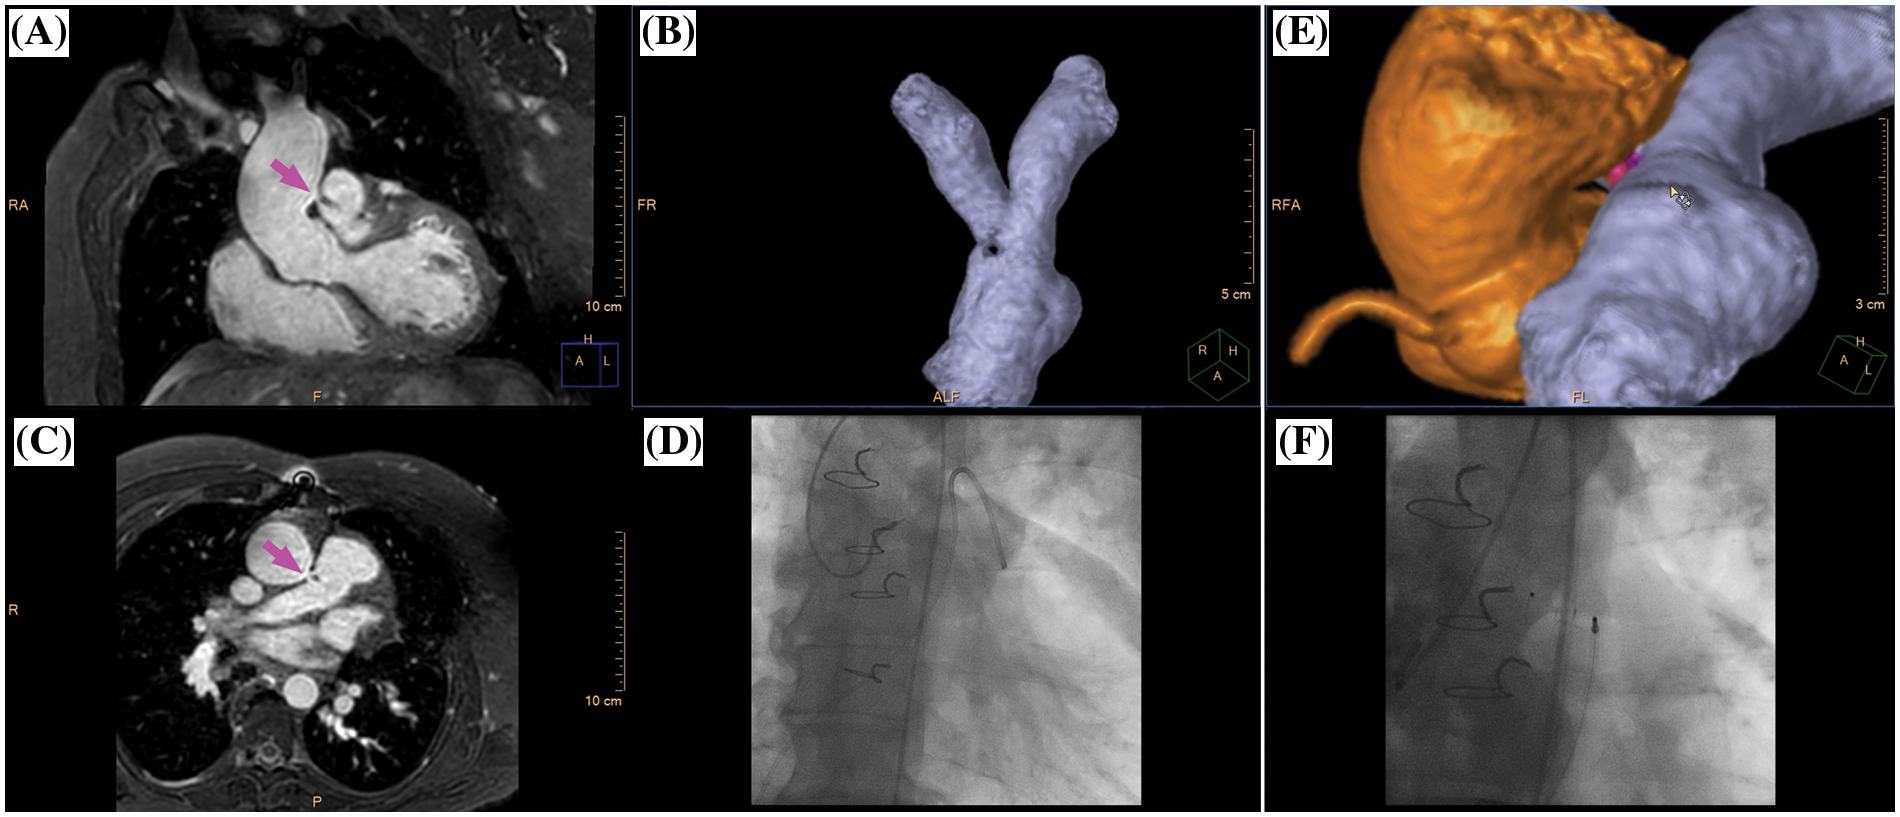

Figure 4: Clinical case example II. (A) Multiplanar-reformatted projectional view of nsWHcs for depiction of the aortopulmonary window (coronal geometry, magenta arrow); (B) volumetric-surface rendering of main pulmonary artery bifurcation with clear demarcation of an intraluminal signal loss resulting from jet-related flow disturbances; (C) multiplanar-reformatted projectional view in transversal geometry at the height of the aortopulmonary window (magenta arrow); (D) X-ray fluoroscopy with semi-selective contrast injection of aortopulmonary window and subsequent pulmonary arterial enhancement; (E) volumetric surface rendering of nsWHcs for 3D display of aortic root/ascending aorta (orange), aortopulmonary window (magenta) and main pulmonary artery/pulmonary arterial bifurcation site (blue); (F) X-ray fluoroscopic angiography of thoracic aorta following occluder implantation of aortopulmonary window. Please refer to video 2 for a fully animated case presentation

Video 2 (.MP4 file)

Clinical case example II (same case as shown in Fig. 4)

A 48-year-old male (bodyweight, 82 kg; heart rate 65/min; diazepam sedation) with prior surgical ventricular septal defect (VSD) closure in early childhood presented with progressive pulmonary hypertension and new-onset atrial flutter raising suspicion of residual VSD. CMR imaging identified extracardiac shunting from an aortopulmonary window (luminal diameter 7 mm) located about 25 mm cranial of the left coronary cusp of the aortic valve with continuous systolic-diastolic jet-related flow disturbances. Percutaneous occluder implantation was successfully performed.